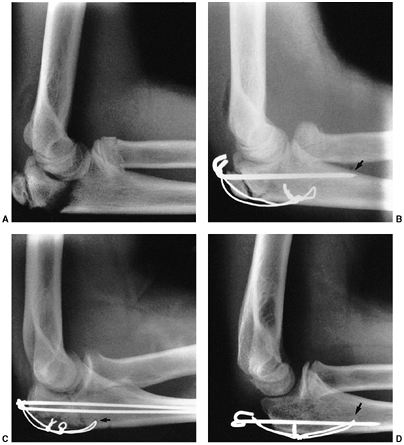

nerve function. Neurovascular problems are frequent, and fracture

management may be altered if neurovascular compromise is present. In

the absence of neurovascular compromise, displaced fractures can be

splinted and managed safely in a delayed manner as long as the child is

closely monitored (132,133). Primary CRPP is the preferred treatment for type III injuries (134) (Fig. 33.18).

Displaced supracondylar fractures treated by closed reduction and

casting have a higher incidence of residual deformity than those

treated with reduction and pinning (134). Closed reduction and casting also has a higher risk of Volkmann ischemic contracture than treatment with early pinning (134).

experience has demonstrated that two or three laterally placed pins are sufficient for stabilization (137).

The authors prefer laterally placed pins without a medial pin except in

unusual circumstances. When a medial pin is used, one should be aware

that extreme elbow flexion could result in ulnar nerve subluxation from

its groove and increase the risk of damage during pinning. When

possible, it is advisable to place the lateral pin first to provide

provisional stability so that the medial pin can be inserted with the

elbow in less than full flexion, placing the ulnar nerve farther

posterior. It is also advisable to make a small incision over the

medial epicondyle and dissect with a hemostat, so that the medial pin

can be placed directly on the bone. Anatomic alignment is preferred,

but this may be difficult to achieve in some cases. When the quality of

reduction is in doubt, comparison radiographs of the opposite elbow can

be obtained intraoperatively. The Baumann angle should be within 5 to 8

degrees of the angle on the contralateral side. As long as fixation is

secure, it is the author’s opinion that one may accept up to one-third

translation of the distal fragment, 30 degrees of malrotation, and 20

degrees of extension after pinning (capitellum anterior to the anterior

humeral line). Initial immobilization should be in a nonconstrictive

splint or cast with the elbow in less than 90 degrees of flexion. The

authors prefer a cast that has been bivalved and spread with the elbow

in approximately 70 degrees of flexion. Oral analgesics are usually

sufficient for pain relief. The need for intravenous narcotics may

indicate ischemia. Immobilization is continued for 3 to 4 weeks, at

which time the pins are removed and active range of motion is initiated.

![]() |

|

Figure 33.18 Type III supracondylar humerus fracture. A: This type III fracture demonstrates lateral displacement. B:

The lateral projection also shows flexion of the distal fragment. The treatment of this less common position is the same as that for extension fractures. The posterior periosteum is torn, and hyperflexion of the elbow will excessively forward-flex the distal fragment. The elbow is best pinned at slightly less than 90 degrees of flexion, because it is technically difficult to pin the elbow in extension. C and D: Anteroposterior and lateral postreduction and pinning films. |

reduction through a medial approach, adding a lateral incision, if

necessary. An anterior surgical interval can also be used, and is

recommended if the neurovascular structures need to be exposed. The

posterior approach should

be

used cautiously because it disrupts any remaining intact soft tissue

and may disrupt the primary vascular supply to the distal humeral

fragment (122,123).

Complete vascular disruption is uncommon, because the thick local

muscle envelope protects the artery. Vascular evaluation after

reduction requires differentiation of the pulseless extremity that is

pink and viable from one that is cold and pale with vascular

insufficiency. The child who has a well-perfused hand but an absent

radial pulse after satisfactory closed reduction does not necessarily

require routine exploration of the brachial artery (129,138,140,141).

The pulse usually returns within 48 hours. Likewise, the absence of a